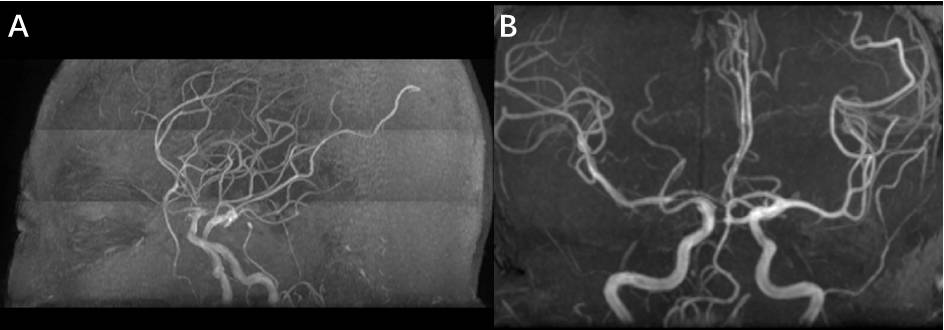

凝血功能及血小板计数均在正常范围内。阅当地医院DSA造影,提示右侧颈内-后交通动脉瘤(图2); 3-D重建后示: 囊性动脉瘤位于右侧颈内动脉-后交通动脉交叉处,前外侧朝向(图3)

图3. 3D重建:囊性动脉瘤位于右侧颈内动脉-后交通动脉交叉处,前外侧朝向。